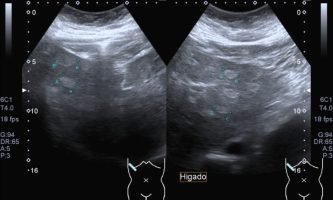

El médico de referencia le indica nueva ecografía de control, donde se observan múltiples y extensas lesiones focales hepáticas hiperecogénicas, redondeadas y confluentes, las cuales predominan en adyacencia a venas supra hepáticas, sin condicionar efecto de masa y sin alteración de la superficie hepática(fig. 1 y 2). Ante la valoración con Doppler color no presenta patrón de flujo peri ni intralesional y respeta el calibre de las venas supra hepáticas(fig. 3 y 4). Dada las características ecográficas se sospecha esteatosis focal multinodular confluente como principal diagnóstico presuntivo, siendo los diagnósticos diferenciales patologías de naturaleza infecciosa, tumoral o metastásica.

El examen radiológico abdominal más comúnmente utilizado en prevención es la ecografía (US) dado que es un método económico y accesible, no invasivo y que no utiliza rayos X, con el cual se logra fácilmente el diagnóstico de esteatosis, dado que se reconoce aumento difuso de ecogenicidad del parénquima hepático. Los criterios principales: la ecogenicidad del parénquima hepático debe ser mayor que la de la corteza renal, mala definición diafragmática, de los vasos supra hepáticos y de la arquitectura intra hepática.2(fig. 8, 9a y 9b)